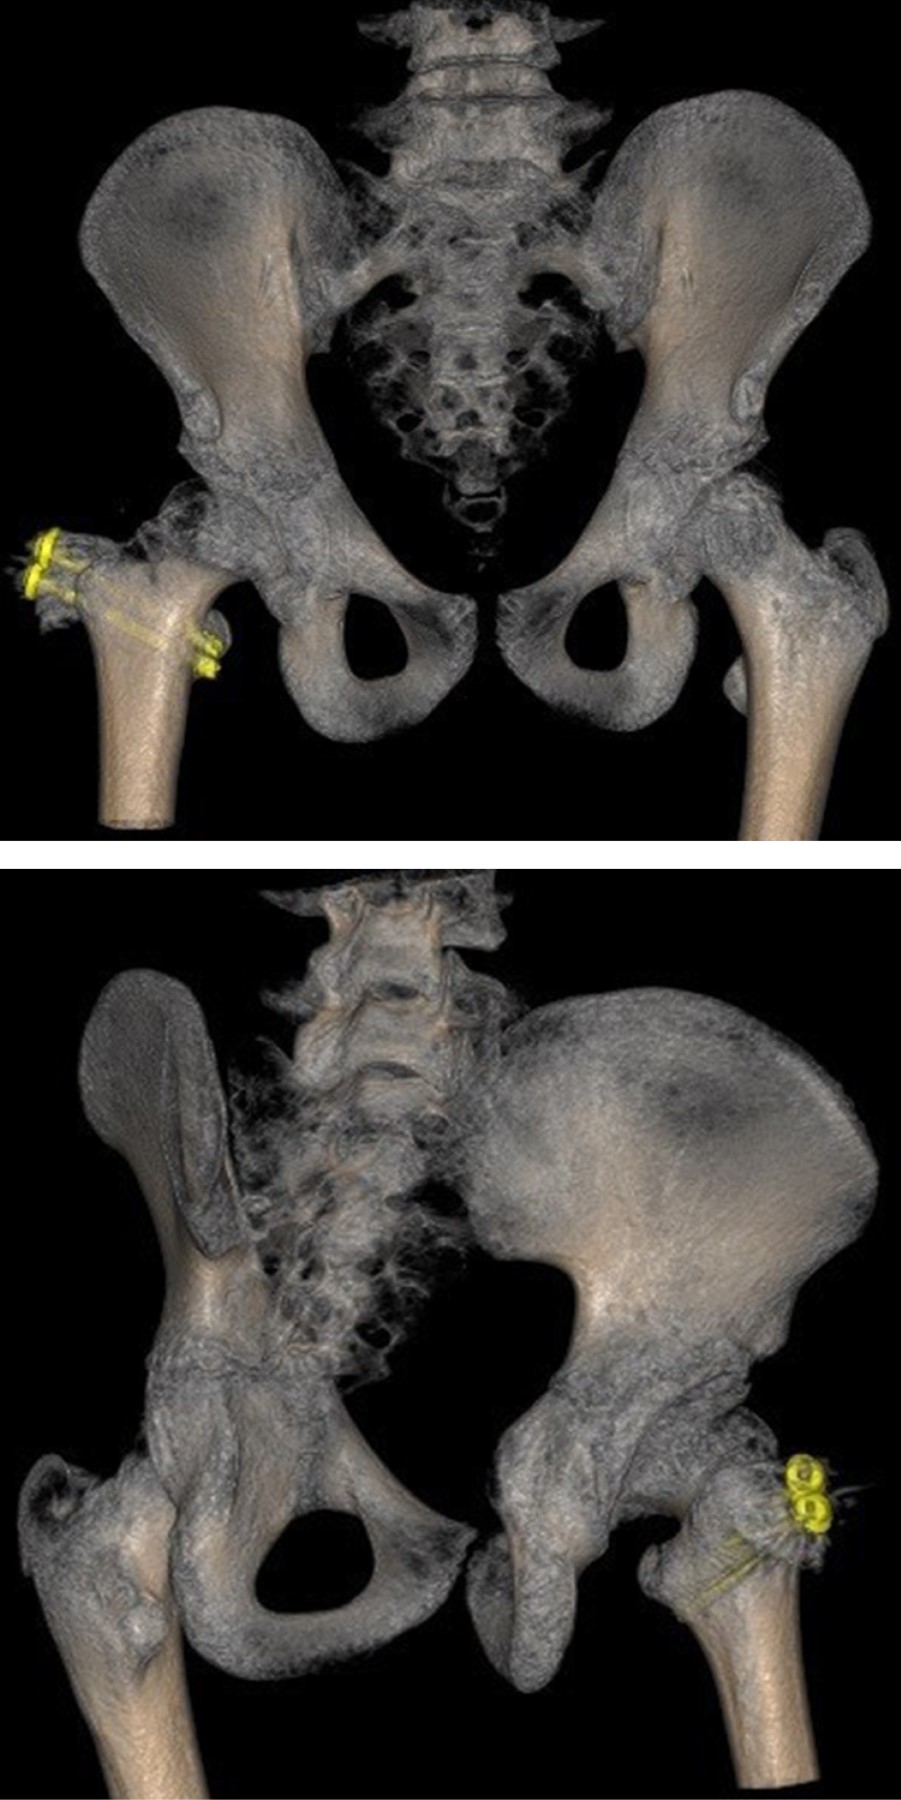

Treatment of femoroacetabular impingement with controlled dislocation of the hip

The femoroacetabular impingement is a syndrome caused by abnormal contact between the femoral head and the acetabulum; it can progress in complications, and the treatment must be individualized with the aim to restore the functionality of the joint. A case of a 12 years old patient who presented clinical findings about impingement, he has history Perthes disease. We performed a surgical hip dislocation technique with femoroplasty. We obtained good results. The clinical and radiographic characteristics of the patient has described and the case resolution.

Figure 2